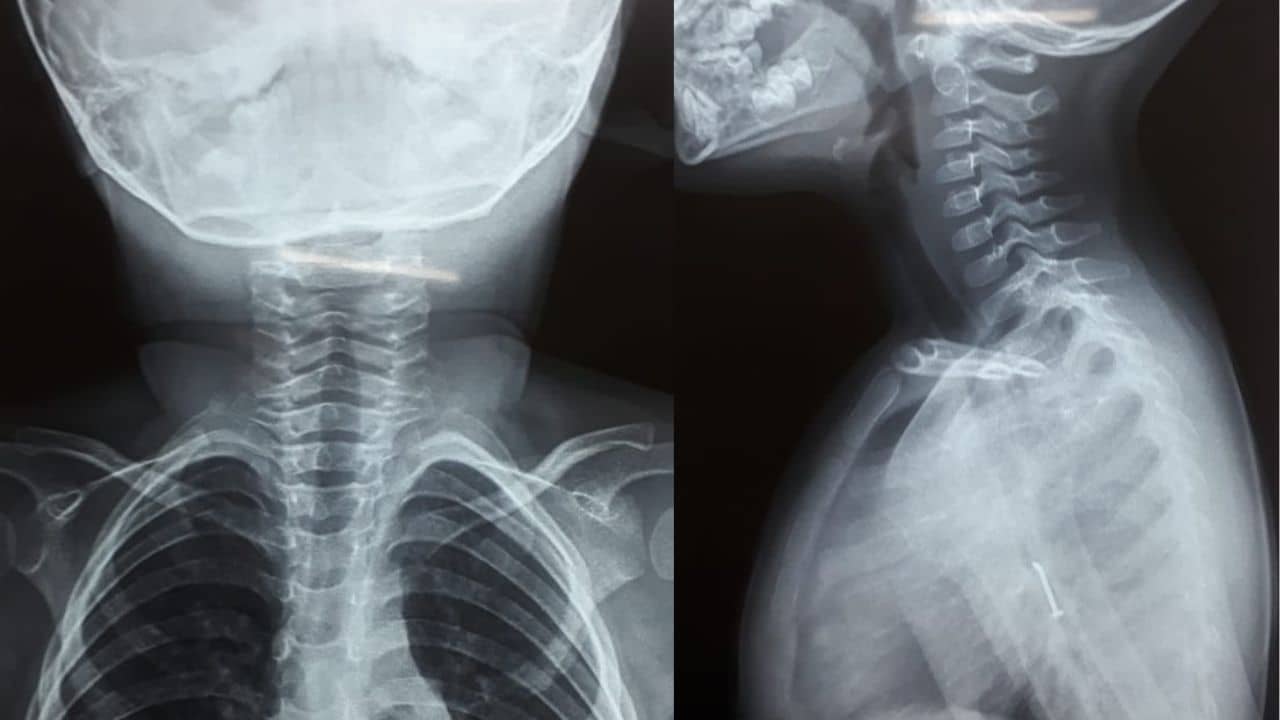

শিলিগুড়ি ডাঙিপাড়ার এলাকার ঘটনা। উত্তরবঙ্গ মেডিক্যাল কলেজ সূত্রে খবর, বুধবার খেলা করতে গিয়ে কোনও ভাবে একটি পেরেক গিলে ফেলে শিশুটি। সঙ্গে-সঙ্গে কাশি শুরু হয় তার। সঙ্গে শ্বাসকষ্টও। পরিবারের সদস্যরা জানতে পারার সঙ্গে-সঙ্গে দেরি করেনি। রাতেই শিশুটিকে চিকিৎসার জন্য নিয়ে আসা হয় মেডিক্যাল কলেজে। ভর্তি করে নেওয়া হয় হাসপাতালে। চিকিৎসকরা এক্স-রে করে পেরেকটির অবস্থান দেখে নেয়।

এরপর বৃহস্পতিবার সকালে বাচ্চাটির জটিল অস্ত্রোপচারের করে সাত চিকিৎসকের একটি দল। তাঁদের কঠোর পরিশ্রমের ফলে অবশেষে বিপদমুক্ত হয় শিশুটি। চিকিৎসক শেখর বন্দ্যোপাধ্যায় জানিয়েছেন, আসলে শিশুটির বয়স কম। এদিকে, অস্ত্রোপচারও জটিল ছিল। তবে সম্মিলিত চিকিৎসার পর আপাতত বিপদমুক্ত শিশুটি। বর্তমানে তাকে পর্যবেক্ষণে রাখা হয়েছে। চিকিৎসক বলেন, “আরিস মহম্মদ নামের একটি শিশু গতকাল পেরেক নিয়ে খেলতে গিলে ফেলে সেটি। এরপর সন্ধে নাগাদ আমাদের ওয়ার্ডে ভর্তি হয় সে। দেরি না করে আমারা তাড়াতাড়ি এক্স-রে, সিটিসি করি তার। সেই সময় দেখতে পাই গলার মধ্যে পেরেক বিঁধে রয়েছে। বাচ্চাটির শ্বাসকষ্টের পাশাপাশি কাশি ছিল প্রচণ্ড। তারপর আমাদের রেডিও লজি বিভাগের প্রধান জানান যে পেরেকটি ফুসফুসের মধ্যে ঢুকে গিয়েছে। এরপর তৎক্ষনাৎ আমরা সাতজনকে নিয়ে একটি দল গঠন করি। আজ সকালে অস্ত্রোপচার করা হয়। পেরেকটি বার করা হয়েছে। এখন শিশুটিকে অবজারভেসনে রাখা আছে।”